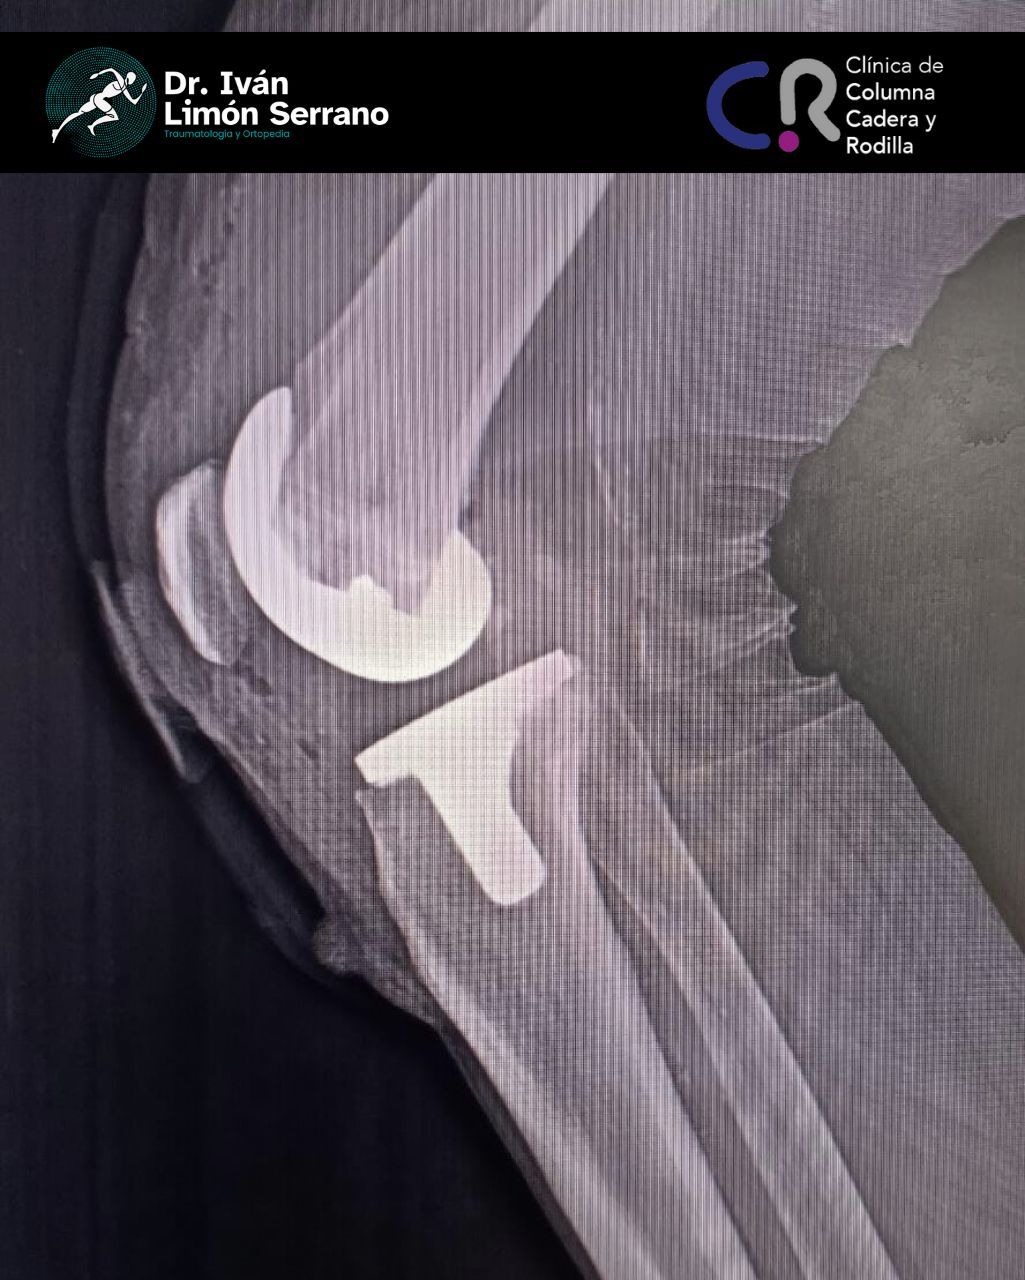

• Prótesis de rodilla

Es una enfermedad articular caracterizada por la por degeneración, perdida del cartílago y alteración del hueso subcondral asociado a cambios en tejidos blandos. Se caracteriza por dolor articular, limitación funcional, crepitación y grados variables de inflamación. Factores de riego como sobrepeso, obesidad, debilidad muscular, actividad física pesada traumatismos, edad avanzada, sexo femenino, factores genéticos, trastornos metabólicos y congénito. Actualmente existen tratamientos desde lo no farmacológico control de peso hasta el tratamiento quirúrgico como lo es el reemplazo articular mediante la colocación de prótesis total.